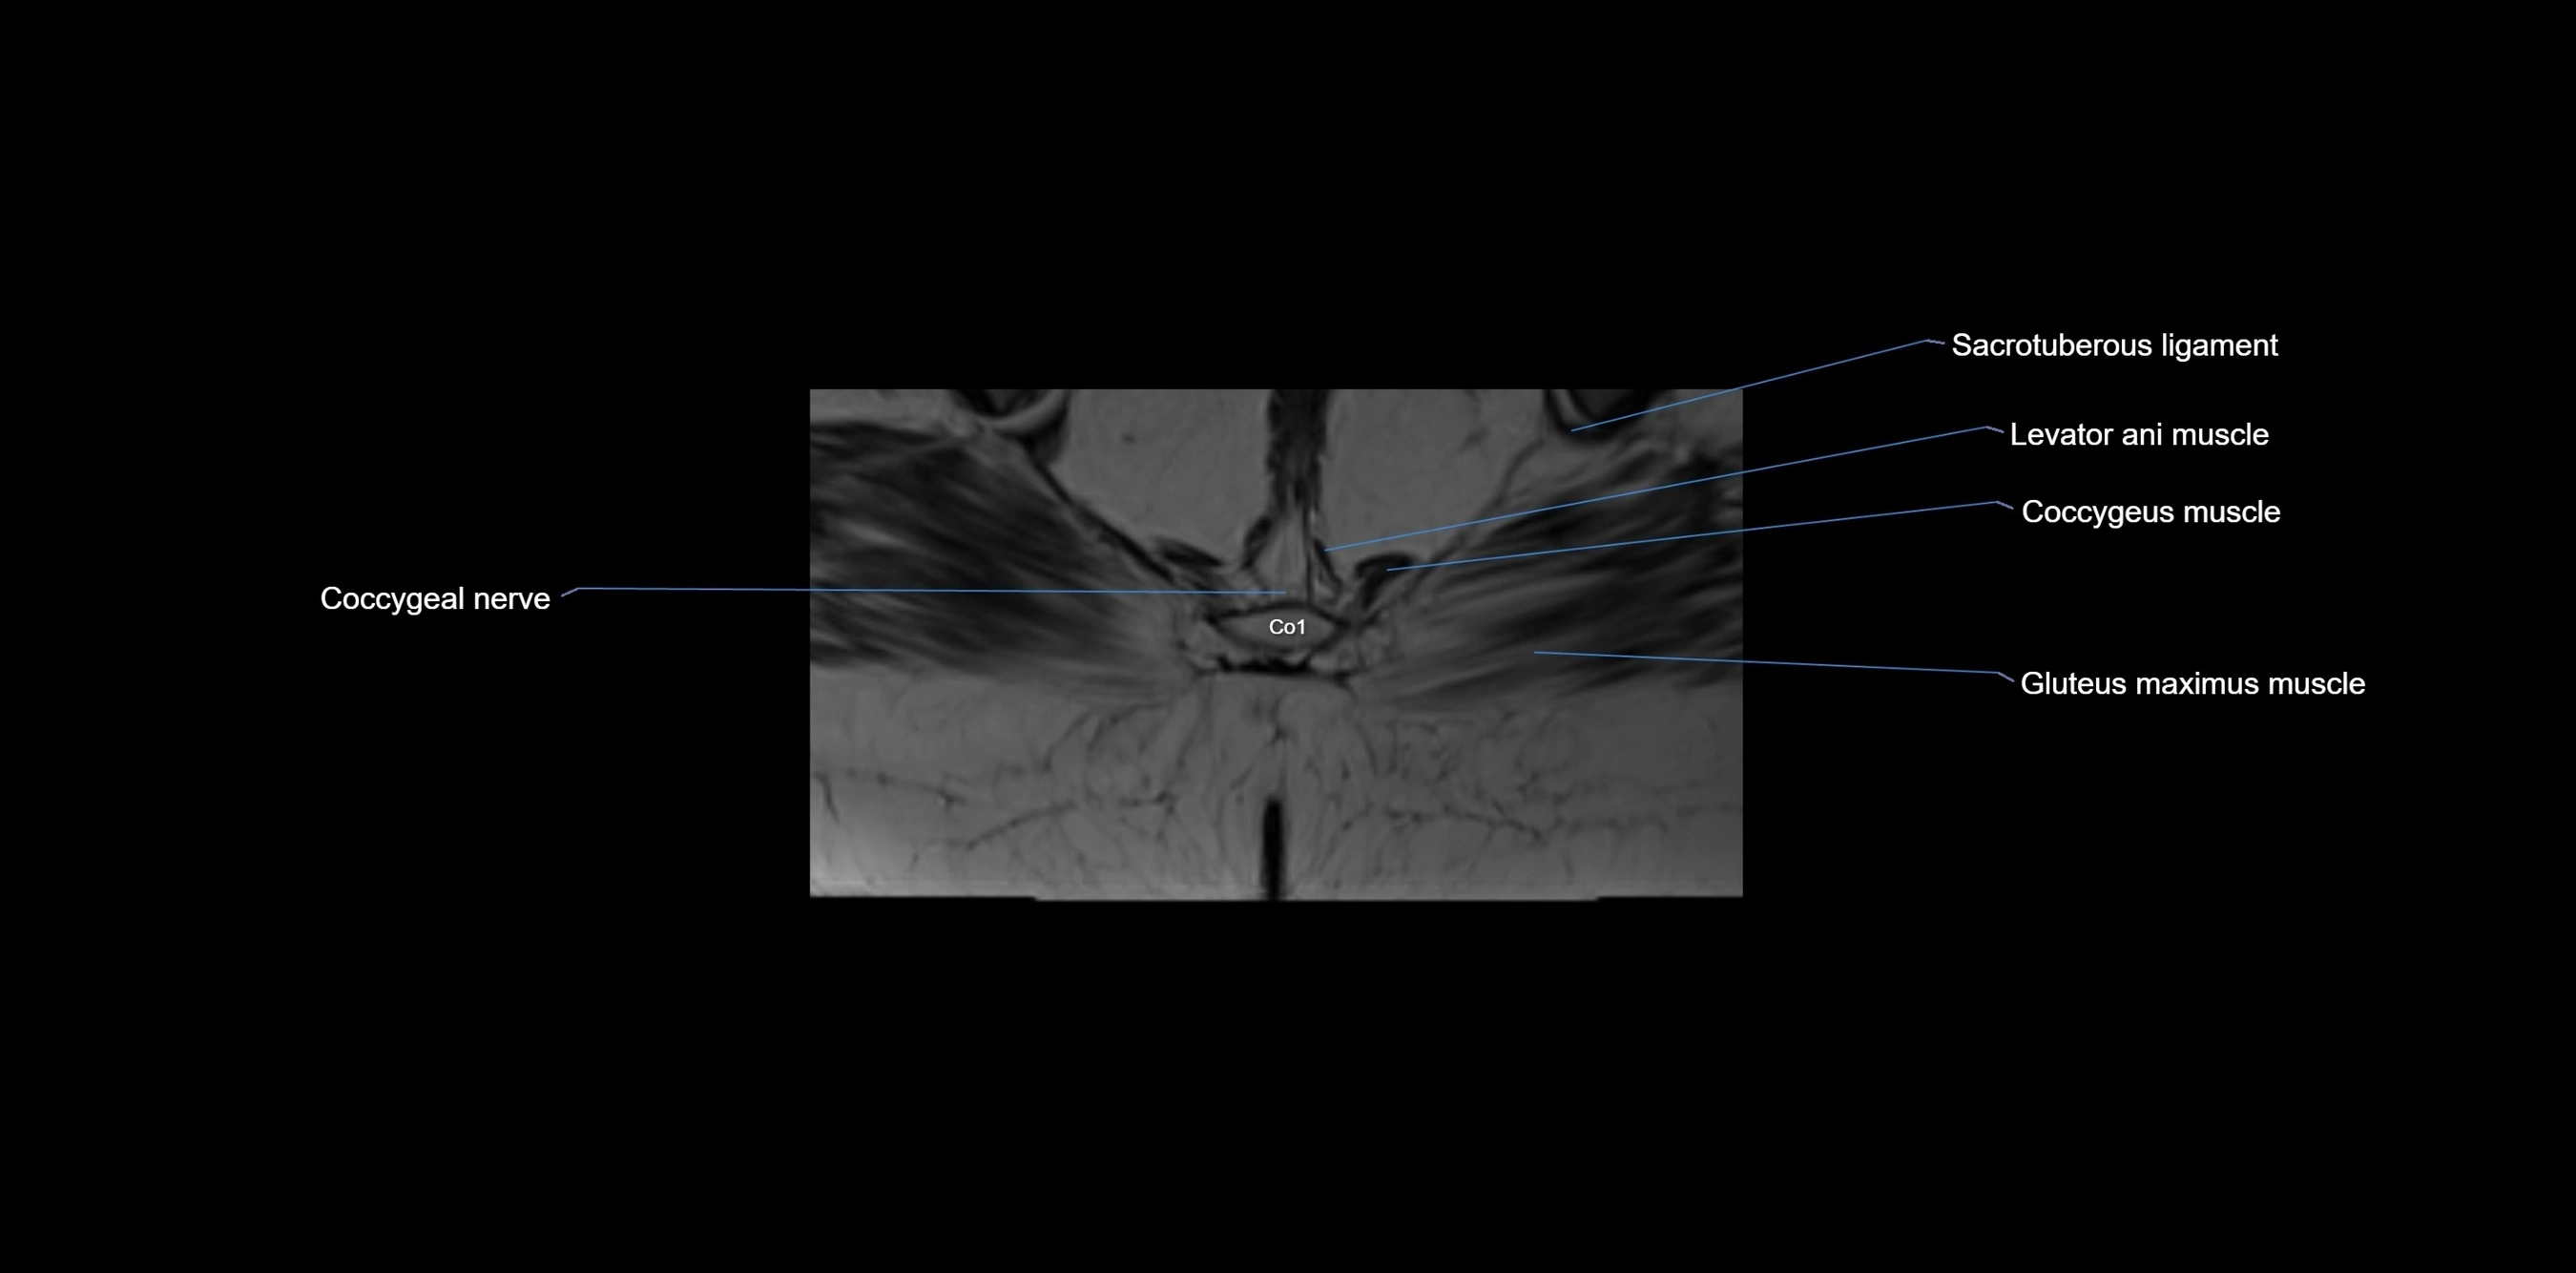

MRI image

image